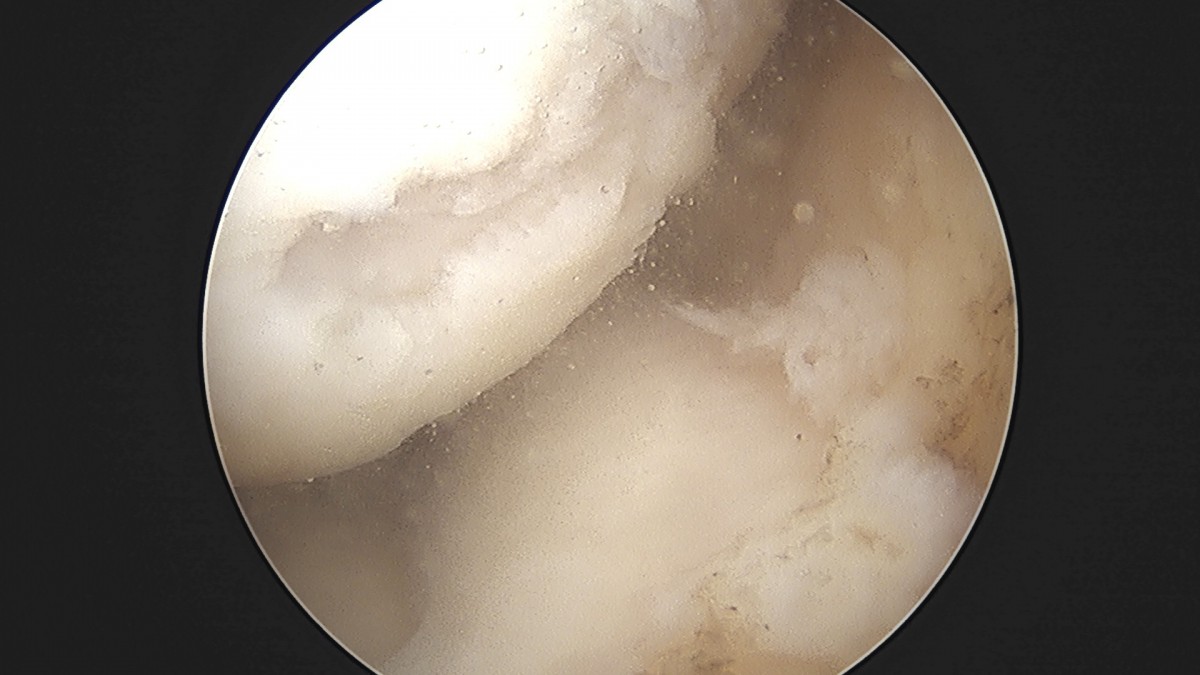

정지영원장님 무릎 반월상 연골판 절제술 이영O 환자

dae765e4d9ac96aee867c9d6292d8784_1758009377_1604.jpg